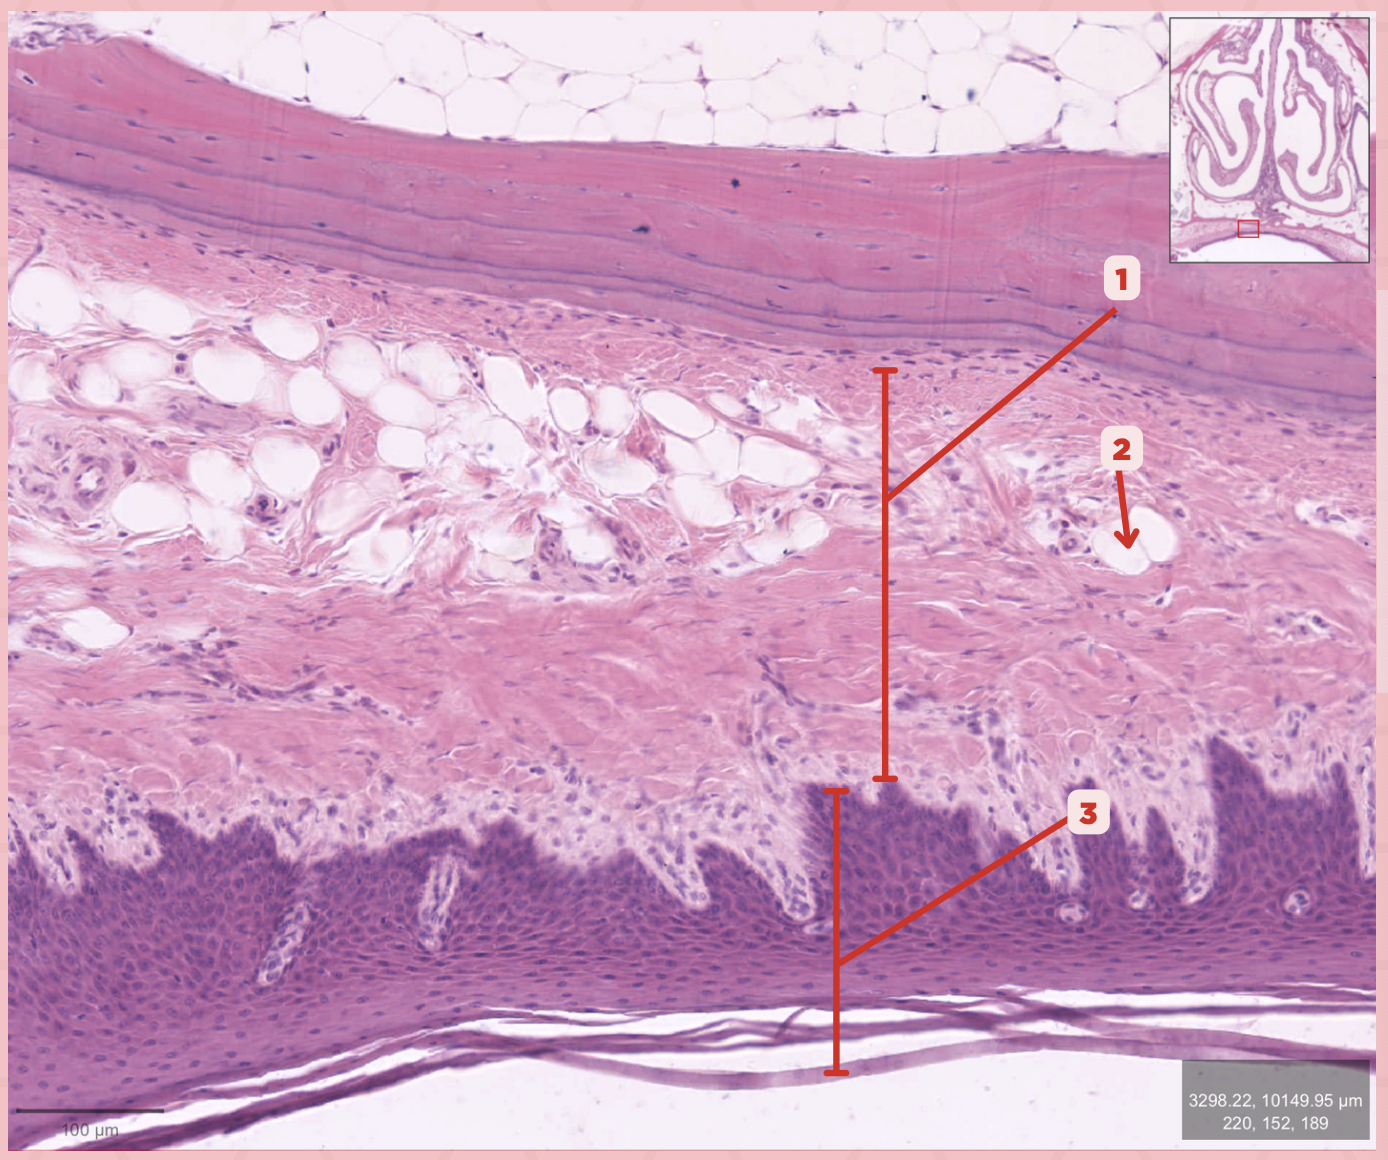

Lamina Propria

Identify the structure labeled as 1.

Adipocytes

Identify the structure labeled as 2.

Keratinized stratified squamous epithelium

Identify the structure labeled as 3.